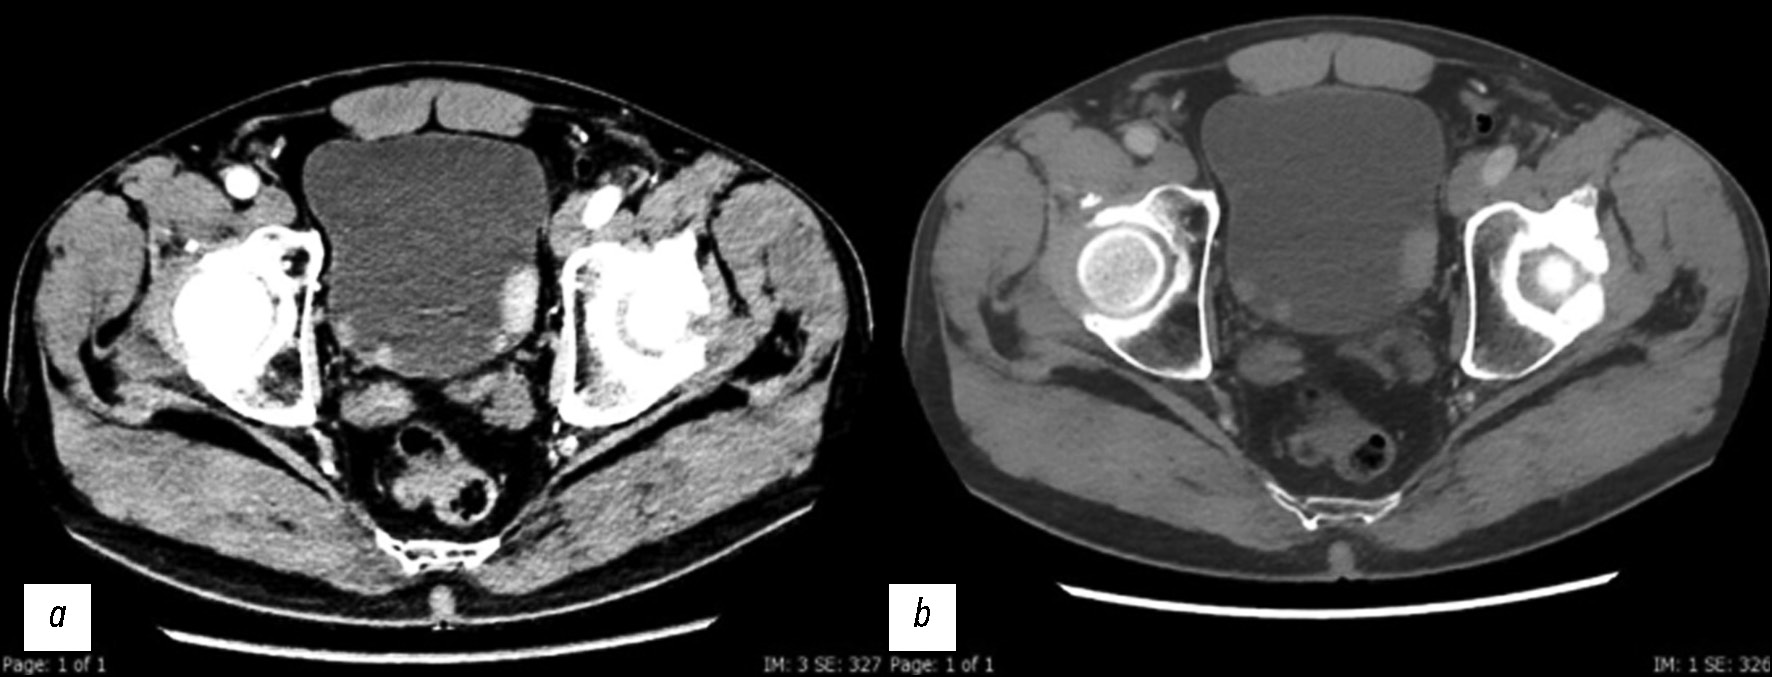

Рис. 8. Компьютерная томография в нефрографической фазе. Её целесообразно использовать для количественной оценки концентрации йода и её нормализации по содержанию йода в аорте: a — йодная карта с демонстрацией нескольких твёрдых узелков на стенке мочевого пузыря; b — йодная карта с наложением цвета для более качественной визуализации очагов. Среднее значение на очаг составляет 1,5 мг/мл, значение Av подвздошной артерии — 8,4 мг/мл, а пороговое значение — 1,3 мг/мл.